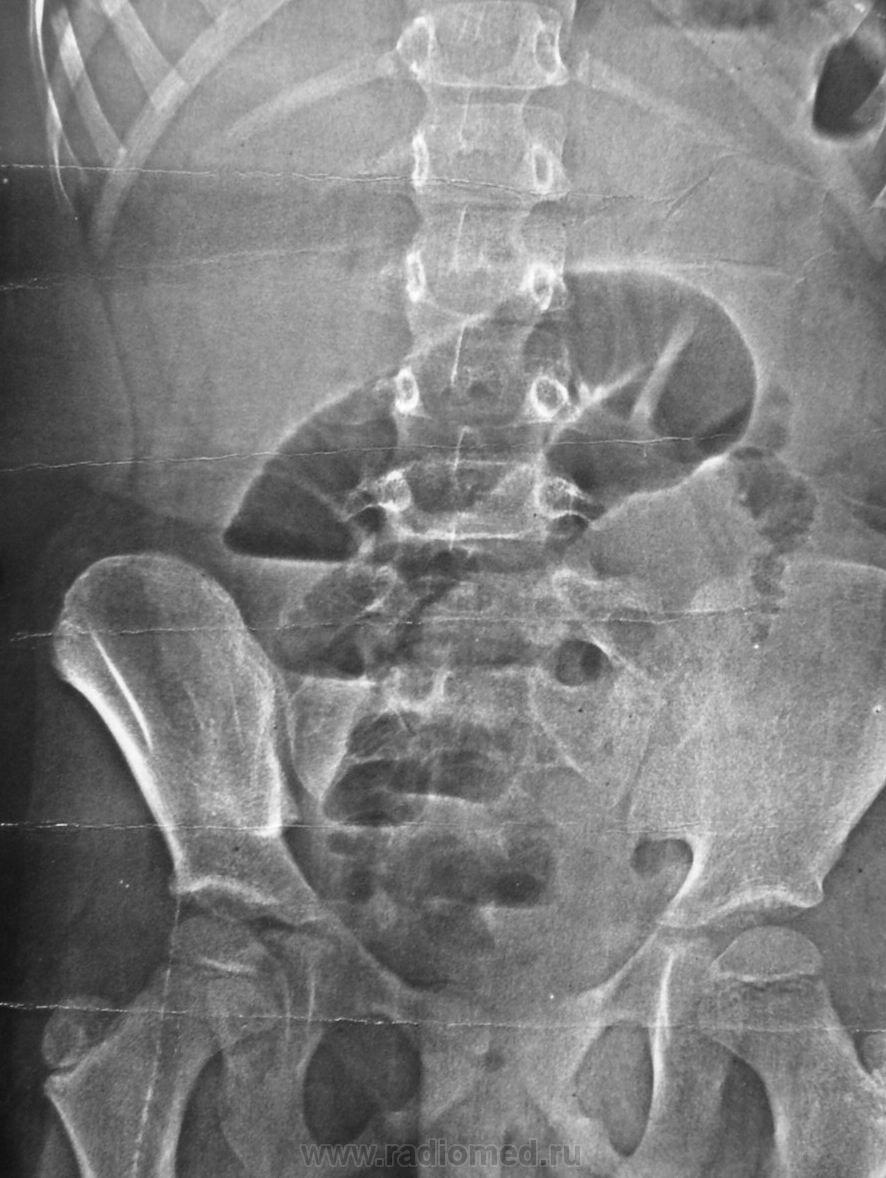

Где-то вблизи слепой кишки препятствие.

На операции - дивертикул Меккеля инвагинировал в тонкую кишку, и все вместе - в восходящую через Баугиневу заслонку. Своевременно, без некроза, расправили, обкололи новокаином, обошлось...